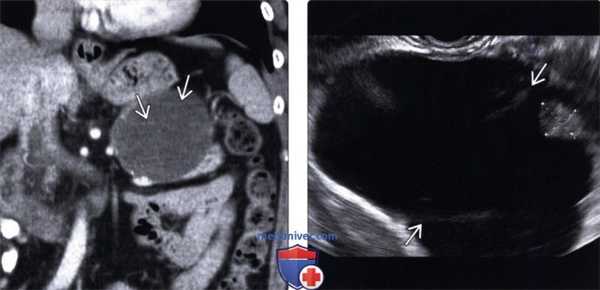

2. УЗИ при муцинозной кистозной опухоли поджелудочной железы:

• УЗИ в черно-белом режиме:

о Четко отграниченное анэхогенное или гипоэхогенное образование, обычно локализующееся в теле или хвосте поджелудочной железы

о Однокамерное или многокамерное с эхогенными перегородками:

- Содержимое кисты может быть анэхогенным или эхогенным, содержать детрит ± солидный компонент

о Не сообщается с системой протоков поджелудочной железы

о Может содержать кальцинаты

о Узловатость стенки указывает на злокачественность новообразования:

- При малигнизации: возможна лимфаденопатия ± толстостенные кистозные новообразования печени

• Цветовая допплерография:

о Новообразование со слабо развитой сосудистой сетью

о Может окружать селезеночную вену или смещать близлежащие сосуды

• Изменения при УЗИ неспецифичны, необходимо дальнейшее обследование - КТ или МРТ

(Левый) На поперечном УЗ срезе брюшной полости в теле поджелудочной железы определяется четко отграниченное анэхогенное кистозное новообразование с единичными периферическими гиперэхогенными очагами. Обратите внимание на неизмененную поджелудочную железу.

(Правый) При КТ с контрастным усилением на аналогичной аксиальной томограмме в теле поджелудочной железы визуализируется кистозное образование овальной формы с контрастной капсулой. Внутри образования имеются перегородки, невидимые на КТ.

(Левый) При КТ с контрастным усилением на корональной томограмме в хвосте поджелудочной железы визуализируется четко отграниченное округлое кистозное образование с плохо различимыми внутренними перегородками.

(Правый) При эндоскопическом УЗИ в той же зоне выявлено крупное кистозное образование с внутренними перегородками и мелким интрамуральным узлом (метки измерителя), не видимыми при КТ.

(Левый) При КТ с контрастным усилением на аксиальной томограмме в хвосте поджелудочной железы определяется четко отграниченное округлое кистозное образование с контрастными плохо различимыми внутренними перегородками.

(Правый) При эндоскопическом УЗИ в хвосте поджелудочной железы выявлено четко отграниченное многокамерное кистозное новообразование с внутренними перегородками.